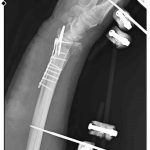

Olay, 29 Aralık günü Mamak’ta meydana geldi. Alınan bilgilere göre, 35 yaşındaki Yasin Arslantaş yaşadığı apartmanın önünde yaklaşık 10 sahipsiz köpek tarafından kovalandı. Kaçmaya çalışırken düşerek el bileği kırılan Arslantaş, ambulansla hastaneye kaldırıldı. Bilek kemiğine 11 adet platin takılan Arslantaş’ın kolunda kalıcı his ve hareket kaybı meydana geldi. Olay nedeniyle maddi ve manevi açıdan zor zamanlar geçirdiği söyleyen Arslantaş, belediye ekiplerinin yaşanan soruna hala çözüm üretmediğini iddia etti.

“Bileğimde 15 dikiş ve 11 platin var”

Yasin Arslantaş, “Sabah apartmandan çıkış yaptığım sırada arkamdan 9 köpeğin geldiğini gördüm. Saldırgan haldelerdi. Bana saldırmak üzerelerdi. Kaçmaya çalışırken ayağım kaydı ve düştüm. Bileğimde 15 dikiş ve 11 platin var. İki ay boyunca kolum bu halde kalacak ve ardından da yine 2 buçuk ay fizik tedavi süreci olacak. Doktorlar his ve hareket kaybımın olacağını söylediler. Bileğimden büyük kemiğin kırılmasından dolayı zorlu bir süreç geçiriyorum. 3 saatlik bir ameliyat geçirdim” dedi.